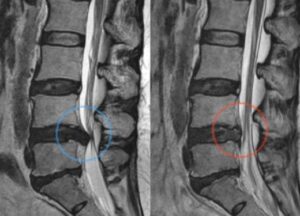

이들의 특징은 통증과 더불어 지배하는 부위의 저림, 차가움, 근육의 불수의적 수축, 근력 약화가 동반 되었을대 강력하게 의심해 볼 수 있다. 신경병증은 보통 하행선이다. 추간판 탈출증은 젊은 나이에서 호발된다. 이유는 수분이 많아서라 볼 수 있다. 벼락을 맞은 듯한 급성 통증과 허리통증, 굴곡시 허리 통증 및 방사통이 심화된다. 시간이 지나면 튀어나온 추간판은 자연적으로 소실된다. 척추관 협착증은 연세 있는 분들한테 나타나기 쉽다. 서서히 진행되는 퇴행성 질환이고 다리저림과 같은 신경 증상을 보인다. 요추 신전시 증상이 악화된다. 걷다 쉬다 걷다 쉬다 하는 ‘간헐적 파행’ 증상을 보인다. 증상이 호전되더라도 협착된 부위의 구조적 호전은 기대하기 어렵다. 척추관 협착증의 특징으로는 요추의 불안정성이 동반된 곳에 호발이 되고, 요추의 불안정성이란 굴곡과 신전시에 특정 요추가 불안정하게 움직임이 있는 것을 말한다. 요추 전방전위증이 보통 그렇다. 구조적으로 돌이킬 수 없는 퇴행성 변화이고 서서히 만성적인 통증의 원인으로 작용한다. 따라서, 요추의 불안정성을 개선시키는 방향으로의 운동전략이 필요하다. 인대가 좁아지며 협착증이 될 가능성이 크다. 추간판 탈출을 일으키는 핵심 움직임은 요추의 굴곡과 신전이다. 요추 신경의 주행경로를 할면 추간판 탈출 증상을 알 수 있다. 좌골 신경통이란 병명이라기 보다는 증상이다. 좌골신경통을 일으키는 질병으로는 허리디스크와 척추관 협착증, 이상근 증후군이 있다. 추간판 탈출증과 협착증 환자 운동의 원칙은 허리 통증을 유발시키는 자세는 피하고, 다리 저림을 악화시키는 자세는 피해야 한다. 정적인 자세 평가를 통해 요추의 불안정성을 개선시키는 운동을 해야한다. 디스크 환자 중 소변이나 대변 장애를 갖고 있거나 보존적 치료로 반응하지 않는 경우 제외하고는 운동을 권하고 있다.